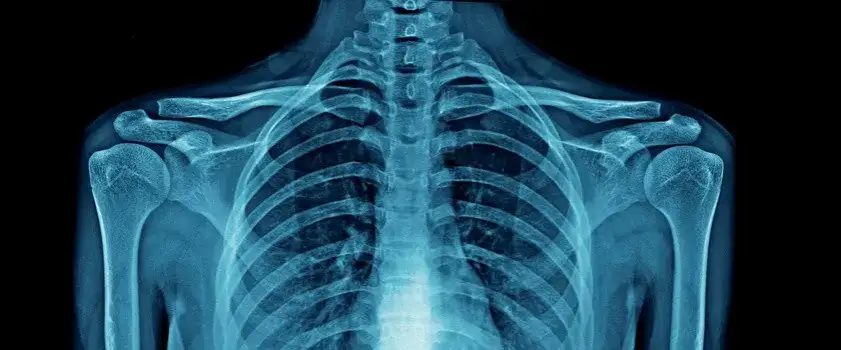

Nadżerka kości, zwana również erozją kostną, to ubytek w powierzchni kości powstający w przebiegu chorób reumatycznych, szczególnie reumatoidalnego zapalenia stawów. Główną przyczyną są procesy zapalne prowadzące do destrukcji tkanki kostnej.

Objawy nadżerek kości mogą być początkowo subtelne, ale z czasem stają się coraz bardziej dokuczliwe. Diagnostyka opiera się głównie na badaniach obrazowych, takich jak RTG, USG czy rezonans magnetyczny. Wczesne wykrycie zmian jest kluczowe dla skutecznego leczenia nadżerek kości.